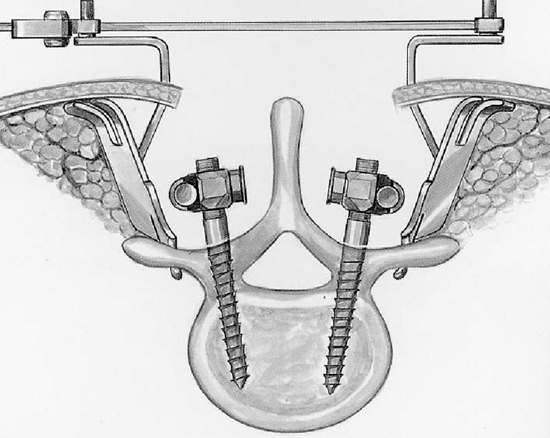

Хирургическое лечение спондилолистеза заключается в фиксации «разболтанных» позвонков титановыми винтами. Винты вводятся в позвонки через дужки позвонков (с лат. «педикули»), поэтому такая фиксация называется «транспедикулярной». Данный метод фиксации позвонков был впервые применен Roy-Camille в 1963г. и используется благодаря своей высокой эффективности по всему миру до настоящих дней.

Рис. 5a. Схема введения винтов через дужки позвонка при транспедикулярной фиксации позвоночника. Рис. 5b. Схема транспедикулярной фиксации L4-L5 позвонков титановой конструкцией. Окончательный вид конструкции в сборе (вид сверху).

Рис. 1a. Схема введения винтов через дужки позвонка при транспедикулярной фиксации позвоночника.

Рис. 1b. Схема транспедикулярной фиксации L5-S1 позвонков титановой конструкцией. Окончательный вид конструкции в сборе (вид сверху)